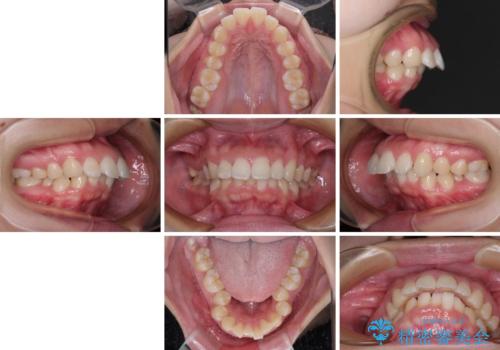

- 上顎前歯が飛び出していて唇がうまく閉じられないとのことで来院された患者様です。

くちばしのように前歯が突出していたため、口元を積極的に引っ込めるために、上下左右の小臼歯4本を抜歯することとしました。

また、上顎歯列が下顎に対して前方位に位置していたため、補助装置を用いて上顎歯列を後方に移動させ、より積極的に口元を下げるようにしました。